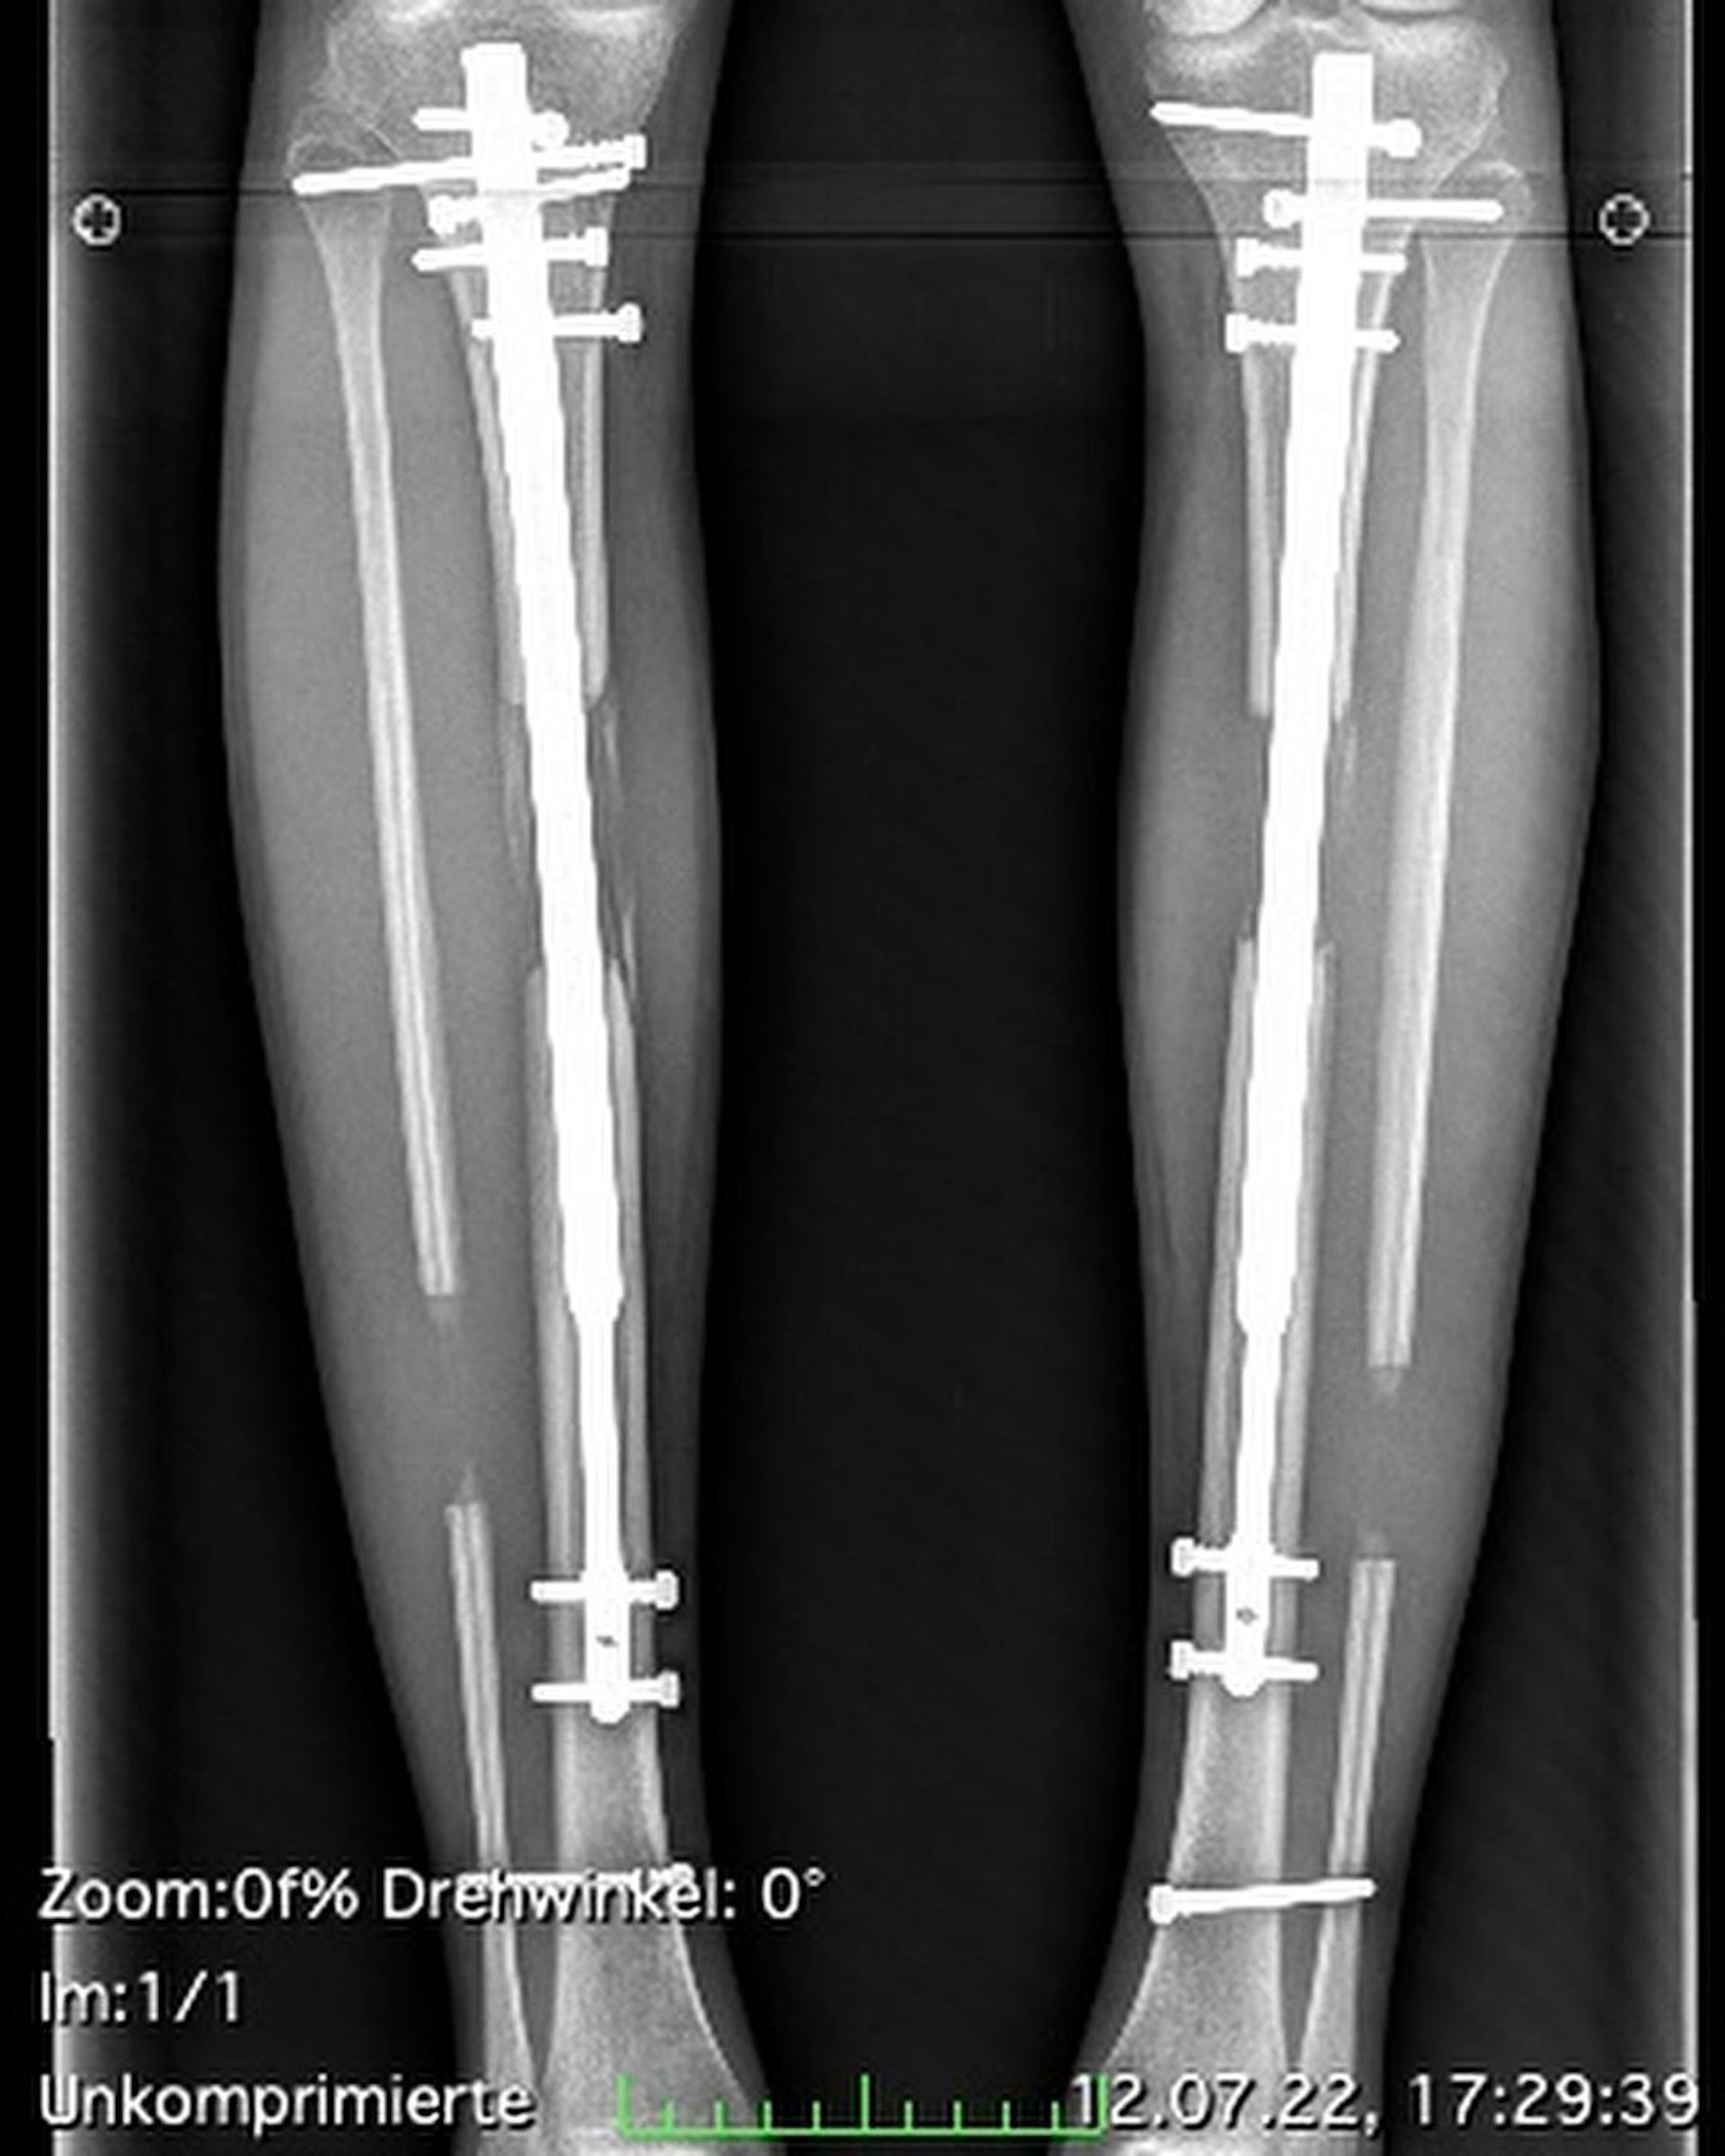

於是,Theresia Fischer豪花過百萬(13萬英鎊)兩度進行增高手術。2016年,第一次接受增高手術,以伸縮桿加長大腿8.5cm;2022年,因雙腳僵硬,只好硬著頭皮進行第二次小腿伸展,再加長了5.5cm。最終從167cm變成身高181的逆天超長腿。

Theresia Fischer事後回想起這段增高過程直言是「惡夢般痛苦」,她指手術令她忍受了許多不必要痛苦:「我的脛骨被打斷,小腿肌肉被撕裂,在裡面還安裝一個可伸縮的裝置,每次行走都會增高裝置所發出的『咔噠咔噠』的聲音。」她更指出,手術後還需要承受即使吃止痛藥都不能忍受的劇痛。這些都是戀愛衝昏頭腦下的決定,令她深感後悔。